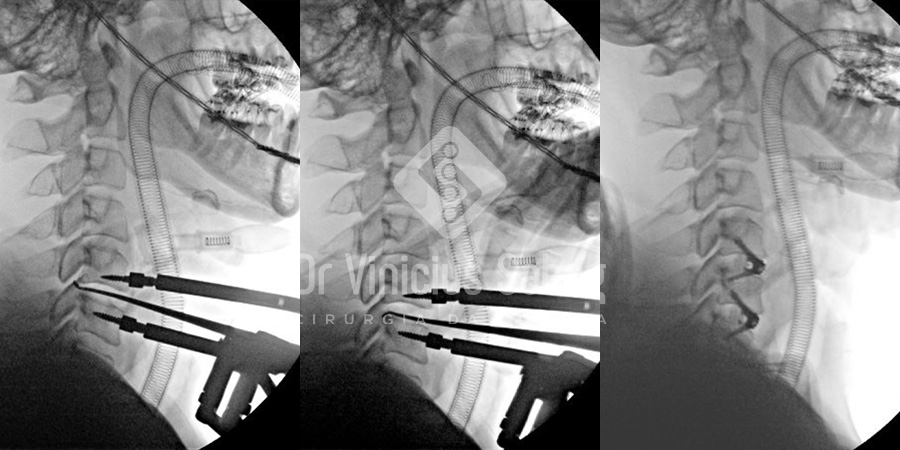

Raio X intraoperatório evidenciando a descompressão da medula e fixação das vértebras cervicais.